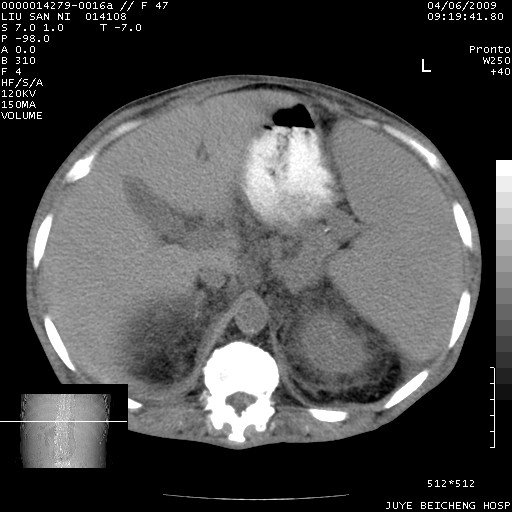

以下是引用前行在2009-4-7 10:31:00的发言:[br]肝脾肿大;双肾增大,双肾盂少量积水可能,肾膜膜增厚,肾周间隙增宽,并见桥间隔,提示结缔组系统疾病、系统性红瘢狼疮肾可能性大。继发右侧胸腔、心包、腹腔积液。

以下是引用深泽交通医院在2009-4-7 11:21:00的发言:[br]双侧肾周密度增高,见条索影,右肾实质见点片状低密度区,考虑弥漫肾炎【自身免疫性?】;;肾性水肿征